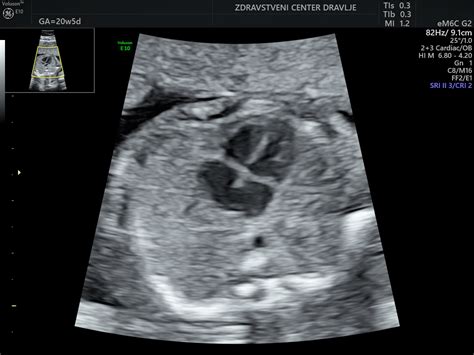

V 35. tednu nosečnosti je dojenček že precej velik. Njegovo velikost lahko primerjamo z ananasom, saj tehta približno 2400 gramov in meri približno 46,5 cm. Čeprav se njegova rast v višino do poroda ne bo bistveno spremenila, bo pridobil še približno en kilogram telesne teže. V tem obdobju je dojenček že udobno nameščen v maternici, kar pomeni, da se njegov položaj proti koncu nosečnosti pogosto ustali. Njegov sluh je popolnoma razvit in najbolje reagira na visoke zvoke. Če pričakujete dečka, je pomembno vedeti, da je praktično že razvit, pljuča pa še vedno dozorevajo v zadnjih tednih nosečnosti. Otrokovi prebavni organi, kot sta ledvici in jetra, že opravljajo svoje naloge. Ledvici odstranjujeta odpadne produkte, jetra pa shranjujejo beljakovine in vitamine ter pretvarjajo sladkor v glukozo. V otrokovem črevesju se začne tvoriti snov, imenovana mekonij, ki je sestavljena iz plodovnice, voskaste mazi, odpadlih dlačic in gostega žolča. Otrokov imunski sistem deluje neodvisno od materinega krvnega obtoka, saj je absorbiral vsa potrebna protitelesa za razvoj odpornosti. Kljub temu pa njegov imunski sistem še ni povsem razvit, kar pomeni, da so dojenčki in majhni otroci še posebej ranljivi za patogene.